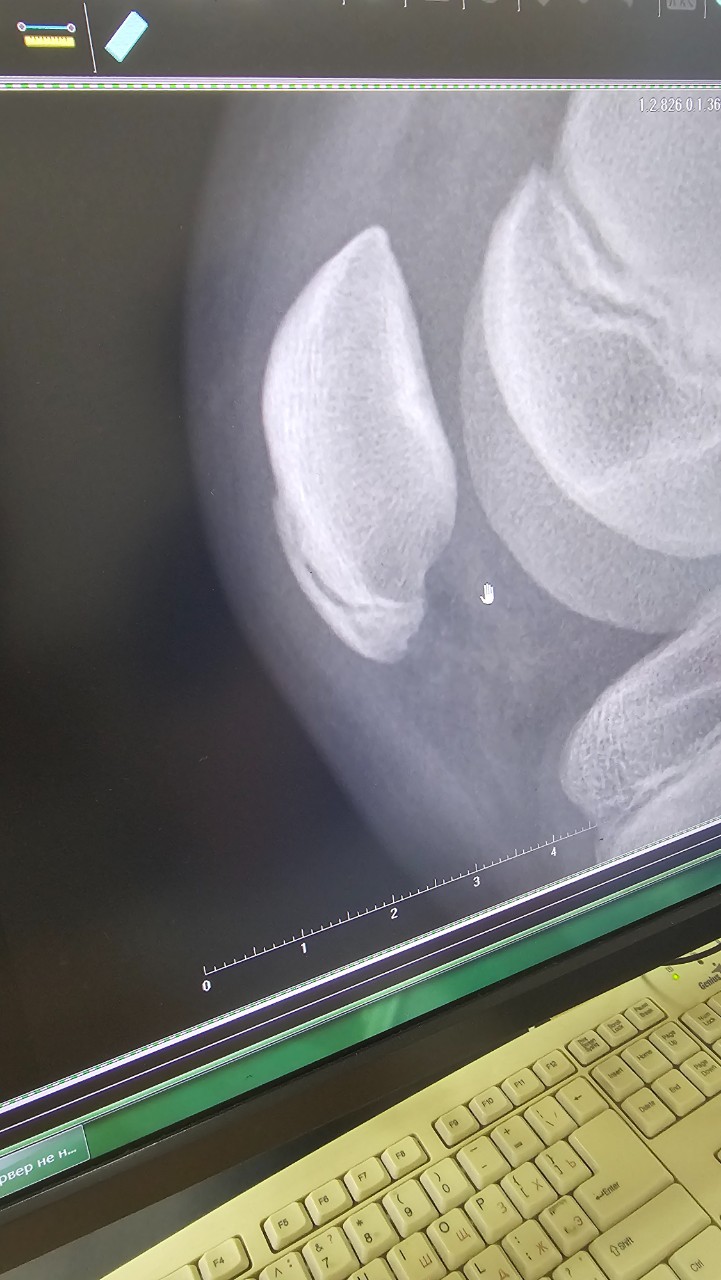

Здравствуйте,2 недели назад ребёнок как он сказал упал на коленко сверху чашечки был синяк, пару дней мазали бодягой и забыли т. к сын больше не жаловался. Позавчера ребёноа пожаловался на дискомфорт за чашечкой как будьто что то происходит, но боли нет. Сегодня колено опухло и на ощупь горячен, побежали к травматологу, сделали снимок. На снмке на самой чашечке как будь то перелом, но врач говорит он бы не смог ни бегать ни ходить, старых травм то же не было, врач сказал не знает что это такое, поставил синовит аоленного сустава и отправил нас к хирургу. Подскажите что это на снимке за перелом и как наи лечиться?